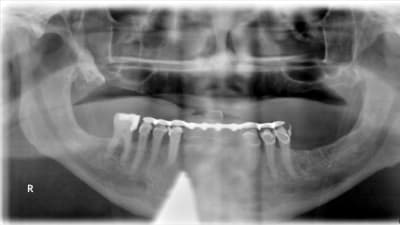

Special Report General Dentistry Digital Imaging Digital Radiography in General Practice: Is It Time to Convert? By Claudio M. Levato, DDS August 01, 2013 9 min read

Special Report Carestream Dental: Innovative Imaging Solutions Benefiting Patients and Practices August 01, 2013 4 min read

Special Report XDR Radiology: Digital Solutions Designed by Dentists for Dentists August 01, 2013 4 min read